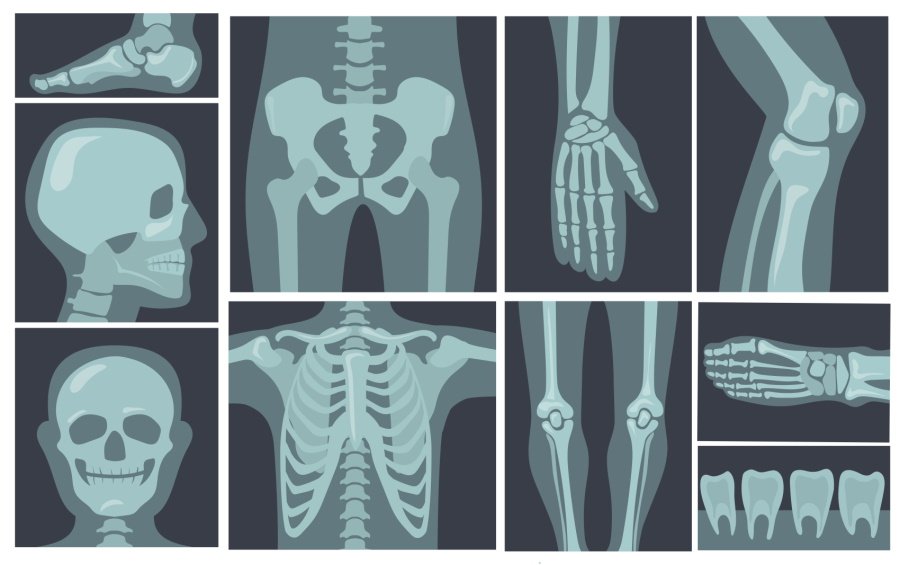

Le système ostéo-articulaire regroupe les os, les articulations, les cartilages et les ligaments. Il est essentiel à la mobilité, à la posture et à la qualité de vie. En naturopathie, on vise à préserver sa souplesse, sa solidité et à prévenir les douleurs chroniques. Les produits Atomy peuvent accompagner cette démarche grâce à des actifs ciblés.

Pourquoi prendre soin du système ostéo-articulaire ?

- Il est soumis à des contraintes mécaniques quotidiennes (marche, posture, sport…).

- Le vieillissement, l’inflammation et les carences peuvent fragiliser les os et les articulations.

- Une bonne santé articulaire favorise l’autonomie, la vitalité et le confort de vie.